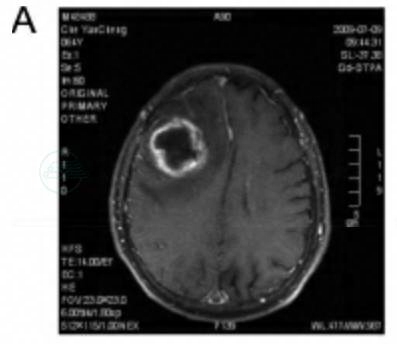

病例A

患者车某,男性,64岁。

主诉:头晕伴左侧肢体乏力、言语模糊2天。

现病史:患者家属诉患者在2天前开始出现头晕,伴左侧肢体乏力,言语模糊。在外院行头颅CT检查见右额顶囊性占位病变,周围大面积水肿。近期无发热病史。

既往史:既往有高血压病和糖尿病病史,口服药物控制良好。

个人史:嗜烟40余年,>20支/日。3个月前曾因一过性房颤在外院治疗后缓解。

体格检查:明显消瘦,言语模糊,定向力尚可,左侧肌力明显下降,上肢约3级,下肢约3级。右侧肢体肌力5级。双侧病理征(+)。

诊疗经过:入院后行MRI检查见右额顶占位病变,内有囊性坏死,增强扫描可见明显环形强化,考虑转移瘤可能性大(图1)。胸片、腹部B超结果未见明显异常。术前病例讨论结果:考虑胶质瘤或颅内转移瘤,不除外脑脓肿。入院第3天行右额顶开颅病变切除,术中穿刺见囊液呈脓性,冰冻结果为“脓性”。保护脑组织后予切除囊壁。术后病理:右额叶脑脓肿(图2)。

图1